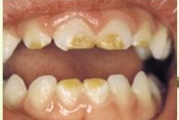

Lutipudelikaariese kahjustused

Lutipudelikaaries